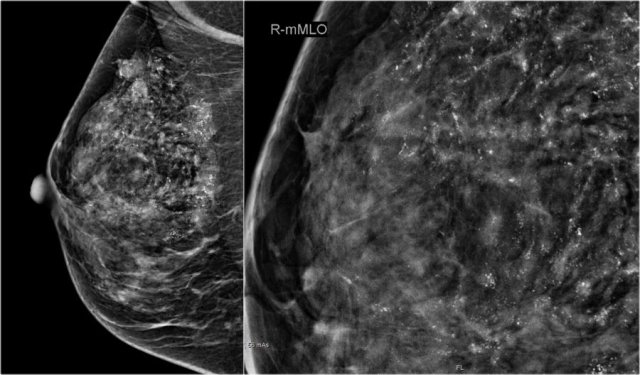

On the mammogram, there is a tumor with secondary skin retraction.

Notice multiple linear calcifications within the tumor - click on image to enlarge. This means that the infiltrating tumor developed within an area of ductal carcinoma in situ or DCIS.

Ultrasound demonstrates tumorfoci within the skin, i.e. T4b (red arrow).